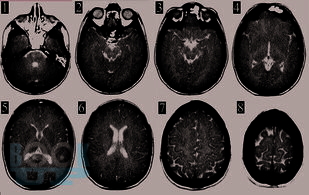

В этой книге мы рассказываем о динамике и взаимосвязи патологических процессов. Эти знания позволяют обосновать вашу тактику. В книге обсуждаются взаимосвязь первичного и вторичного повреждения мозга. Как внутричерепная гипертензия приводит к дислокациям и вклинениям головного мозга и/или нарушениям кровоснабжения мозга. Обсуждается регуляция тонуса сосудов мозга в норме и патологии. Зависимость церебрального перфузионного давления от среднего артериального давления, внутричерепного давления и сохранности ауторегуляции тонуса мозговых сосудов. Рассматриваем варианты отека мозга и возможности лечения. Мы рассказываем как на основе результатов мониторинга внутричерепного давления принимаются решения о том как лечить пациента.